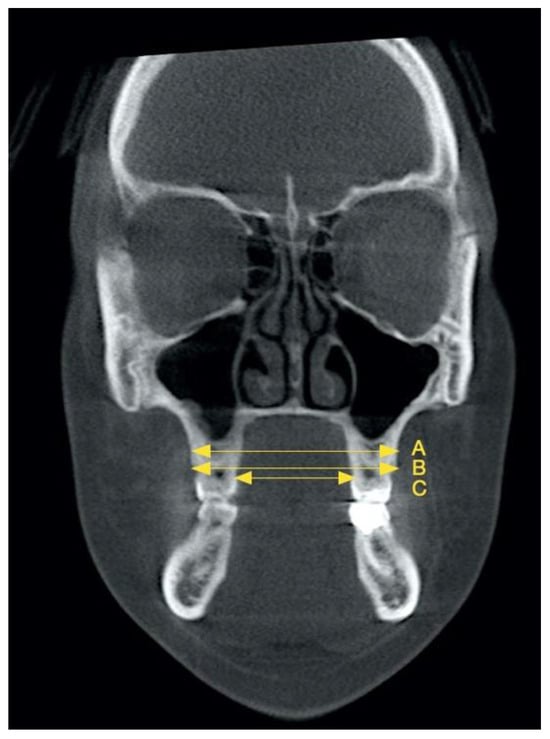

| Maxillary Linear Width | T1-T0 (mm) (Mean ± SD) | T1-T0 Minimum–Maximum Values (mm) | T1-T0 (%) (Mean ± SD) | T1-T0 Minimum–Maximum Values (%) | p-Value |

|---|---|---|---|---|---|

| Alveolar bone | 0.09 ± 0.22 | 0–1.20 | 0.14 ± 0.39 | 0–2.04 | 0.009 * |

| Buccal alveolar ridge | 1.01 ± 0.38 | 0.30–2.80 | 1.80 ± 0.69 | 0.53 ± 5.03 | 2.83857 × 10−24 ** |

| Palatal alveolar ridge | 0.81 ± 0.37 | 0–1.30 | 2.24 ± 1.04 | 0–4.05 | 2.08145 × 10−20 ** |